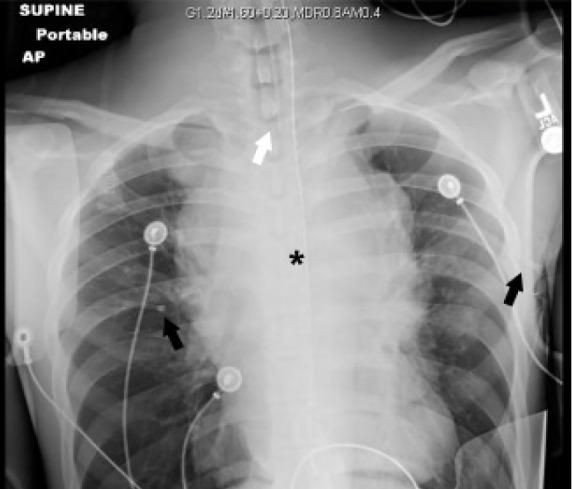

A 20-year-old man with a reported history of asthma presented to the emergency department in cardiac arrest presumed to be caused by respiratory failure.

The patient was discovered to have central airway obstruction and concomitant superior vena cava compression caused by a large mediastinal mass-a condition termed mediastinal mass syndrome. While the patient regained spontaneous circulation after endotracheal intubation, he was challenging to ventilate requiring escalating interventions to maintain adequate ventilation.